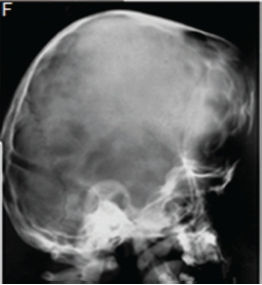

A diagnosis of Apert syndrome was made. Apert syndrome is a rare developmental condition characterized by premature cranial synostosis and resultant growth disturbances. Signs of Apert syndrome include a peaked and vertically elongated head, widespread bulging eyes, and a protuberant frontal region with an anteroposterior ridge overhanging the frontal eminence (Figure A). The palate is high, arched and occasionally cleft (Figure B). There is hypoplasia of the maxilla with relative prognatism of the mandible. Dental malocclusions with crowding and delayed dental eruption in the maxilla are common (Figure C). The facial angle is exaggerated; the nose is small and has been compared to a parrot's beak in appearance. Hypertelorism, exophthalmos and divergent strabismus are often present; sometimes with blindness. Spina bifida has been recorded in some patients. Syndactyly of the hands and feet varies greatly. Hand films in Apert syndrome showing syndactyly with fusion of three fingers in both hands and webbing (Figure D). Syndactyly of the feet in the same patient is also discernible (Figure E) Note the tall (turricephalic) skull, open metopic suture, and faint beaten-silver appearance of the calvarium. Skull base and roof of the calvarium are flattened, with a noticeable beaten-silver appearance (Figure F). The 3-D CT reconstruction of the same patient showing hypoplastic maxilla with posterior cleft (Figure G) The patient may be retarded or of normal intelligence. Apert syndrome may be associated with advanced paternal age. The cardinal radiologic features of Apert syndrome are: Brachycephalic (reduced anteroposterior dimension of the skull with increased skull width). Turricephaly (occurrence of a skull with high vertical index), beaten silver appearance of the calvarium, absence of demonstrable cranial sutures in coronal dimension in young patients, hypoplastic maxilla and syndactyly of the hands and feet. Differential Diagnosis: Crouzon's disease, Pfeifer syndrome, Carpenter syndrome and Summit syndrome.